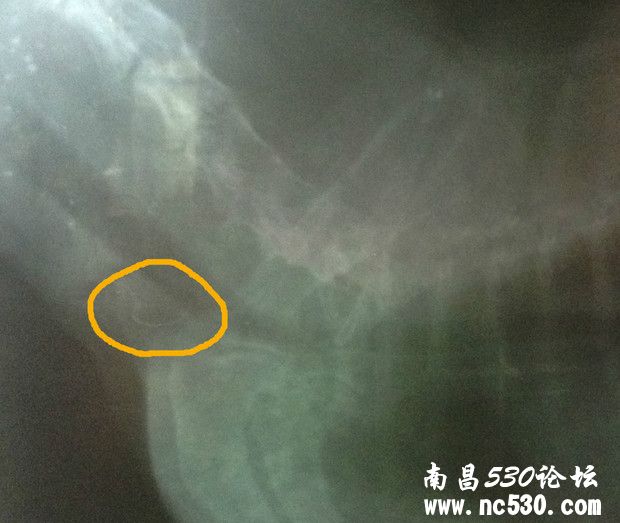

还有就是今天回来仔细看片子,发现下图那块(喉咙还是气管那下面我圈起来的地方)有块东西,也不知道是片子是脏的还是它身上的?特意放上来请各位专家医生看看。说实话,那天医生也没和我讲清楚,连查血那些的单子也没给我,病历也未给写,片子我还是走的时候要求要的。